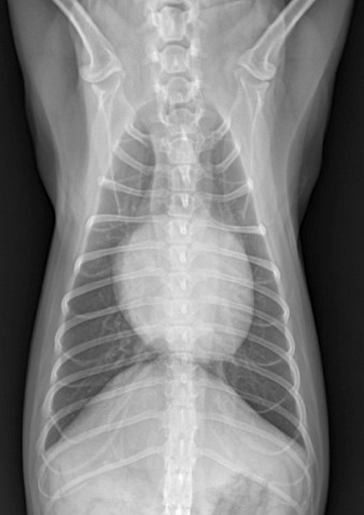

방사선 사진

• RV와 RA 사이 : 삼첨판(tricuspid valve)

• LV와 LA 사이 : 이첨판(mitral valve)

• posterior valve < anterior valve (더 길다)

• 활 모양으로 열렸다 닫히며 심방 → 심실로 혈액을 내보냄.

• 양쪽 valve가 다 이상하면(bivalvular disesase), 양쪽 심방에서 dilation → 심장이 계란 모양에서 valentine shape, heart shape으로 변함.

1기 (Moderate : 좌심방귀 볼록한 정도)

1) 심장 커짐

Cardiomegaly, left auricle 확장, 전허리/후허리 소실 : 심장이 부풀면서 일자형이 됨.

+ Sternal contact : 심장과 sternum 거리 좁아짐

Left auricle 확장, cranial/caudal waist 소실, Globoid heart, Cardiomegaly

3기 (Severe : 좌심실까지 확실히 커짐)

1) 좌심방-좌심실 경계가 사라지고 흉벽과 가까워짐 ⇒ 우심부전까지 발생.

2) Tracheal elevation도 매우 뚜렷.

- Mitral & Tricuspid valve 모두 이상 ⇒ Lt. & Rt. atrium 모두 볼록

- Lt. auricle, LA 확장 ⇒ Trachea elevation, Caudal waist 소실, tall heart